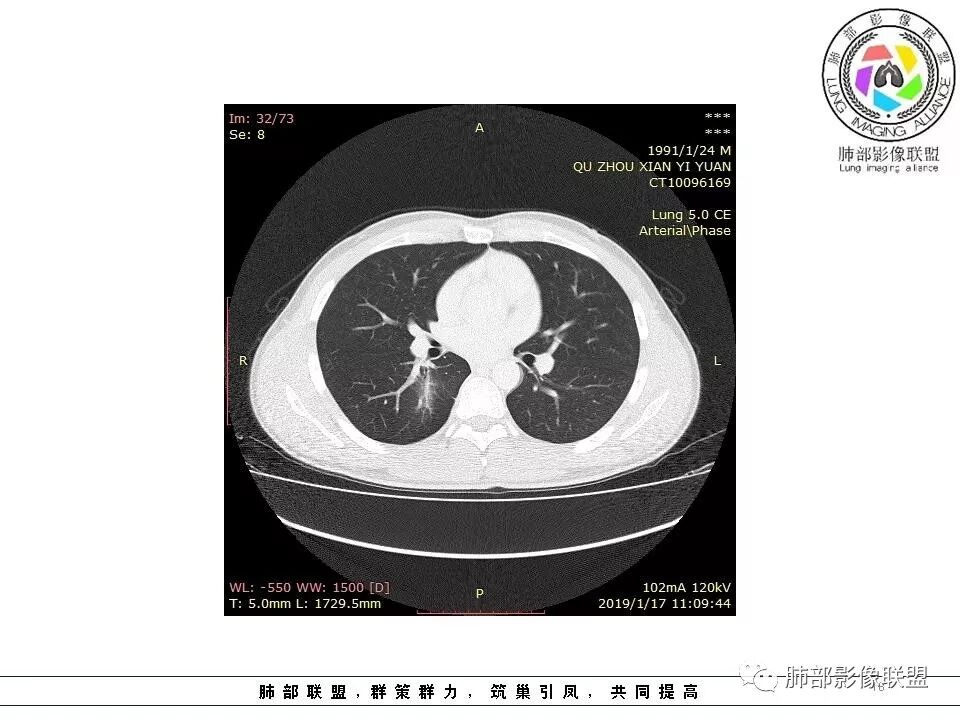

青年男性,间断胸痛;右侧脊柱旁可见一类圆形软组织密度影,密度欠均匀,增强扫描呈轻中度持续强化,邻近肺组织及肺动脉推移,可见肋间动脉供血,部分胸膜下脂肪可见,部分层面似见与右侧椎间孔相连。考虑后纵隔神经源性肿瘤。

青年男性,间断胸痛。右后纵膈脊柱旁软组织占位,形态规则类圆,边缘光整,肺组织受压,D字征,胸膜尾,肋间动脉供血。中度不均匀延迟强化。无支气管进入考虑来源于肺外、肿块与脊柱间未见明显脂肪间隙,考虑来源于胸膜外,考虑神经源性肿瘤,建议穿刺活检。

青年男性,右侧脊柱旁软组织肿块,边缘膨隆,密度不均,临近肺组织受压、胸膜增厚,增强后动脉期呈不均匀强化,并可见肋间动脉供血,延迟期强化较均匀,定位肺外,首先考虑SFT,神经源性肿瘤待排

右上肺野脊柱旁软组织肿块,边缘光滑整齐,肺组织及气管右肺上叶支气管受压前移,外移,边缘可见胸膜尾征,病灶内密度不均,增强后渐进性持续强化,其内可见明显蛇纹血管征,首先考虑肺外来源,sft.可能性大

边缘光滑,宽基底与胸壁相连,跨叶裂,叶裂稍前推,血管、支气管前移。

肋间动脉供血,强化尚均匀,逐步强化

3.相邻椎间孔未见扩大,也未见块影延入椎管,易起自于神经根的鞘瘤似乎找不到支持点。

可惜未提供矢状位骨窗图像,如在肋骨内下缘观察到压迹有助于肋间神经的鞘瘤的判断,这是因为二者之间密切的毗邻关系。

4.静脉期轻度不均匀强化,注意不是环形强化,亦未见明确的“AB区”,这点也不支持神经鞘瘤。临床及病灶轻度强化都不支持副节瘤。